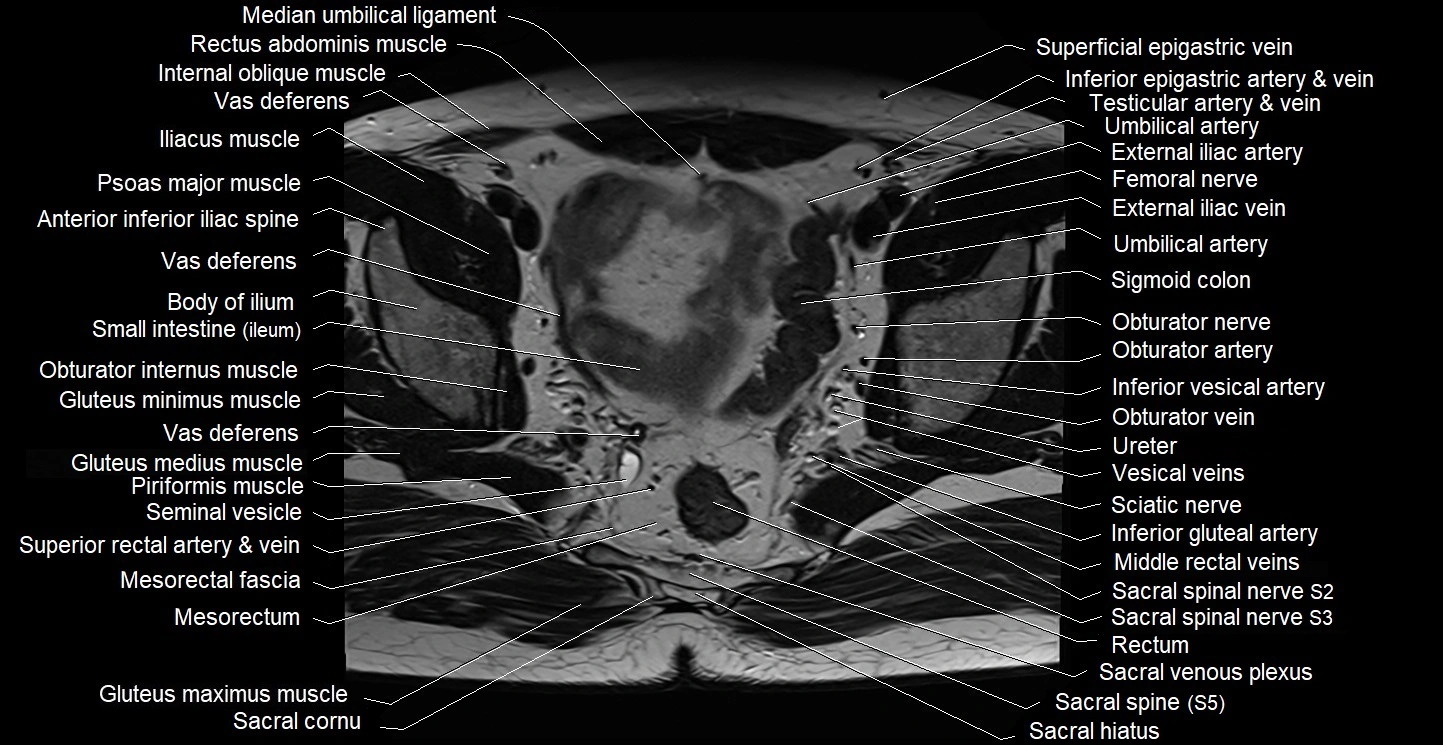

- Median umbilical ligament

- Mesorectal fascia

- Mesorectum

- Obturator internus muscle

- Obturator nerve

- Piriformis muscle

- Sacral plexus

- Sciatic nerve

- Seminal vesicle

- Sigmoid colon

- Spinal nerve S2

- Spinal nerve S3

- Vas deferens

- Vesical veins

- Vesical venous plexus